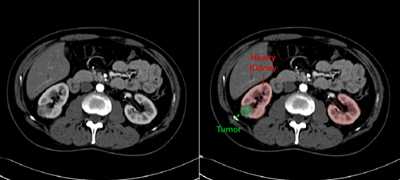

With the most advanced MRI and CT technology, Hackensack Meridian Health uroradiologists (radiologists who specialize in conditions of the urinary tract) partner with your care team to make an accurate diagnosis. This includes:

- Determining whether a mass is solid (which can indicate a cancerous or non-cancerous tumor) or fluid filled (which can indicate a non-cancerous cyst)

- Diagnosing with great precision the size and stage of any tumors in the kidney

- Distinguishing tumors that need surgery and tumors that are candidates for active surveillance

- Detecting any cancer that has spread beyond the kidney